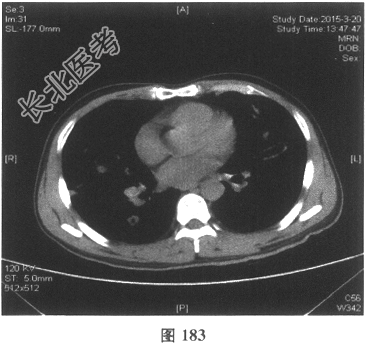

- [材料题] 患者男性,52岁,因间断发热伴咳嗽,咳少许黄痰,无咯血,伴胸闷憋气20余天就诊。体检:体温37.6~38.3℃。既往体健。查体:体温37.6℃,心率83次/分,呼吸20次/分,血压117/64mmHg。神志清,精神可,口唇无发绀;双肺呼吸音粗,可闻及广泛干、湿性啰音,以干啰音为主;心率83次/分,律齐,各瓣膜听诊区未闻及病理性杂音;腹软,无压痛及反跳痛,肠鸣音3次/分,双下肢无水肿。血常规检查:白细胞计数26.32×109/L,中性粒细胞0.846,血红蛋白117g/L,血小板计数1911×109/L;C反应蛋白119.05mg/L。尿常规检查:隐血2(+),蛋白1(+)。痰培养:曲霉菌属,请排除污染。生化全套检查:白蛋白19.6g/L,谷丙转氨酶24.2U/L,谷草转氨酶25.8U/L,γ-谷氨酰基转移酶91.4U/L;尿素氮13.00mmol/L(2.14~7.14mmol/L),肌酐166.8μmol/L(31~132μmol/L);血钾5.6mmol/L。肺部CT见图178~图185。

- 多项选择题4.[提示]患者应用多种抗生素治疗(第三代头孢菌素、青霉素加酶抑制剂)包括抗曲霉菌治疗无效,加用甲泼尼龙40mg静脉滴注病情好转。肺部CT检查显示病变明显改善。尿常规检查正常, 肾功能检测正常。复查肺部CT(图188~图195):示病变较前好转。Wegener肉芽肿的主要临床表现是( )